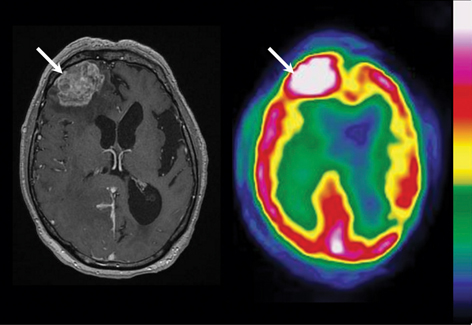

PET enables better identification of intra-tumor heterogeneity compared with standard MRI in addition to delineating tumor extent with much greater accuracy. The identification of malignant foci, commonly defined as “hot spots” in heterogeneous gliomas and a specific characteristic of glioblastomas (58), is essential for biopsy planning. The objective is to ensure that the most biologically aggressive portion of the tumor, which ultimately determines the patient’s prognosis as well as treatment, is not under-sampled (56, 59). Similar to the delineation of tumor extent, amino acid tracers are more suitable than 18F-FDG in identifying malignant foci in gliomas. In a study aimed at guiding stereotactic brain biopsy of gliomas by using 18F-FDG and 11C-MET, the authors showed that all 32 gliomas, 10 of which were glioblastomas, exhibited an area of abnormal 11C-MET uptake, whereas only 7 glioblastomas showed abnormal 18F-FDG uptake (60). An example of superiority of 11C-MET in comparison to 18F-FDG is given in Figure 2. In another study aimed at comparing performances with MRI, stereotactic PET-guided biopsies were also performed with 18F-FDOPA PET. Thirteen of the 16 high-grade biopsy specimens were obtained from regions of elevated 18F-FDOPA uptake, while MRI contrast enhancement was present in only 6 of the aforementioned 16 samples (56). These observations, in accordance with previous results, thus underscore the potential benefit of using PET amino acid tracers in determining the most aggressive portion of the tumor.

Fig 2

Figure 2 PET performed with 18F-FDG (A) and 11C-MET (B) in a 62-year-old woman with a glioblastoma in the left prerolandic cortical area. Uptake of 18F-FDG was reduced in the tumor area except for one area of uptake equivalent to that in the surrounding gray matter. Uptake of 11C-MET was higher in the tumor than in the surrounding cortex, allowing the definition of a target for biopsy. When PET images obtained with the two tracers were co-recorded, the highest focus of 11C-MET uptake corresponded to the hot spot of 18F-FDG uptake (intersecting lines). (Adapted from J Nucl Med 2004;45:1293–1298. Copyright: The Society of Nuclear Medicine and Molecular Imaging, Inc. Reproduced with Permission.)